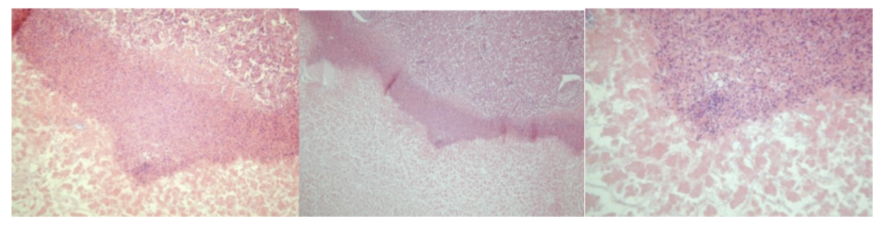

Leucosis lymphadenoidea hepatis - lymphosarcoma

one end of liver → basophilic stained tumor tissue formed by slightly differentiated lymphocytes